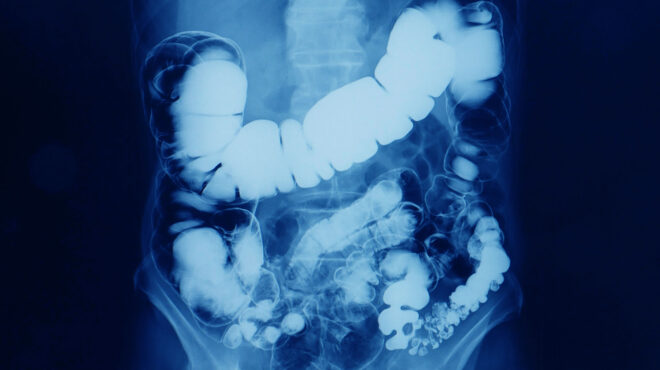

Το πρόγραμμα στοχεύει στην πρόληψη του καρκίνου του παχέος εντέρου και απευθύνεται σε 2,8 εκατομμύρια άνδρες και γυναίκες, ηλικίας 50-69 ετών.

Περιλαμβάνει δωρεάν εξέταση με ειδικά τεστ αυτοδιαγνωστικού ελέγχου (self-test) που θα μπορούν οι πολίτες να προμηθεύονται από τα συνεργαζόμενα φαρμακεία. Σε περίπτωση κατά την οποία προκύψει θετικό αποτέλεσμα από την αυτοδιαγνωστική δοκιμασία (self-test), θα δίνεται η δυνατότητα για δωρεάν επίσκεψη σε συνεργαζόμενο γαστρεντερολόγο/ενδοσκόπο για κλινική αξιολόγηση.

Επιπλέον, ανάλογα με την κλινική αξιολόγηση, περιλαμβάνεται δωρεάν διενέργεια διαγνωστικής κολονοσκόπησης, καθώς και δωρεάν εξέταση βιοψίας σε περίπτωση ευρημάτων, σύμφωνα πάντα με τις συστάσεις της Επιτροπής Εμπειρογνωμόνων Δημόσιας Υγείας (ΕΕΔΥ).